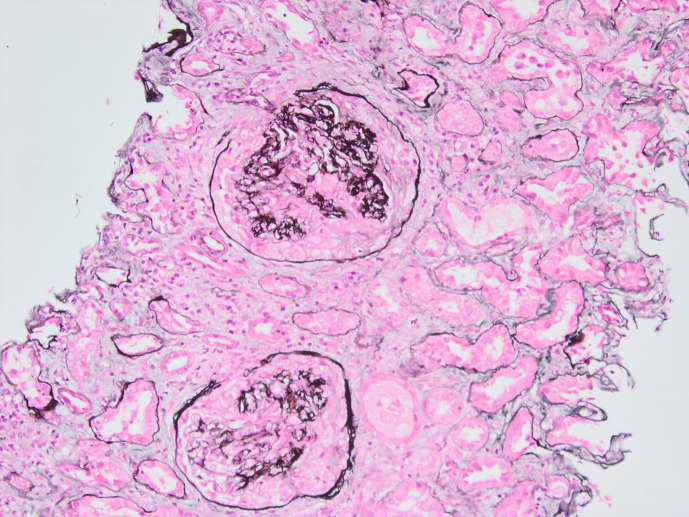

Case presentation: We present the case of a 67-year-old man with rapidly progressive glomerulonephritis requiring haemodialysis at presentation. Serological testing was positive for anti-myeloperoxidase and negative for IgG anti-GBM antibodies. Kidney biopsy revealed necrotizing crescentic glomerulonephritis with linear staining of IgA along the GBM. He was treated with a combination of immunosuppression and plasma exchange and was able to become dialysis-independent.

Conclusion: To our knowledge, this is the first documented "double-positive" IgA anti-GBM disease and ANCA-associated glomerulonephritis.